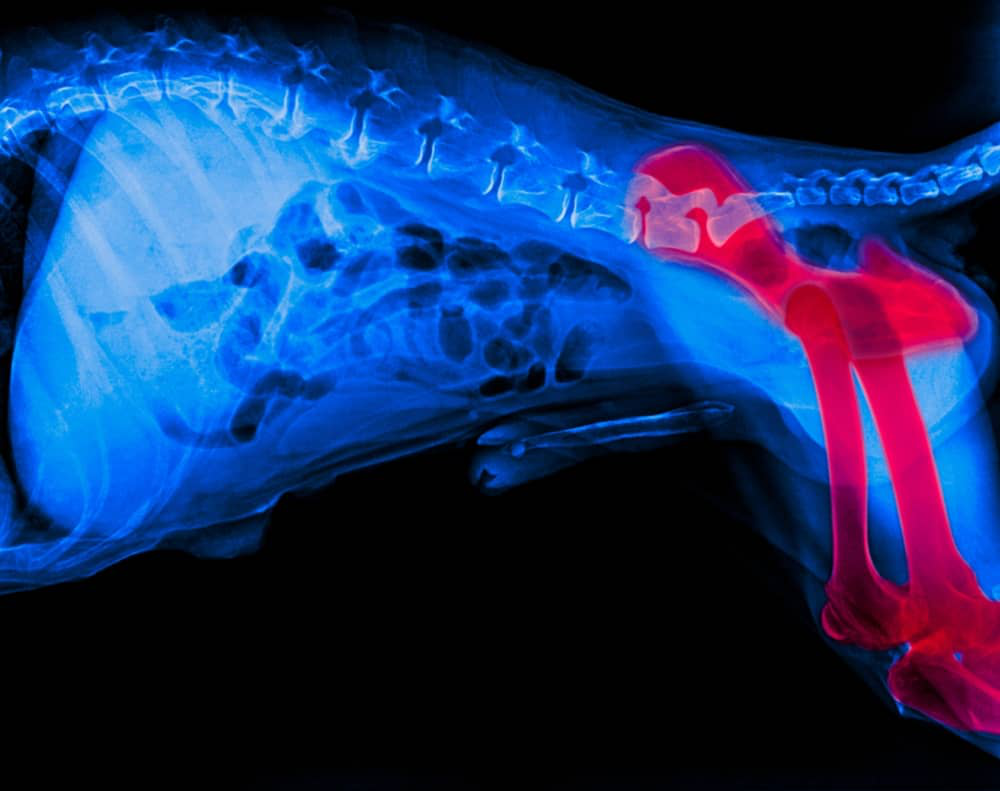

BLOCCO O DEBOLEZZA DELLE ZAMPE POSTERIORI

In alcuni casi, il problema può riguardare esclusivamente le zampe posteriori del cane. Di seguito analizzeremo le principali ragioni di questa condizione.

Le cause della perdita improvvisa dell’uso delle zampe posteriori sono numerose e possono dipendere dall'età, dalla razza o dallo stato di salute generale dell'animale.

Problemi neurologici

Ernie discali: frequenti in razze come i bassotti, possono comprimere il midollo spinale.

Tumori spinali: responsabili di debolezza o paralisi.

Mielopatia degenerativa: una malattia che causa danni irreversibili ai nervi.

Ictus: provoca perdita improvvisa di forza in uno o più arti.